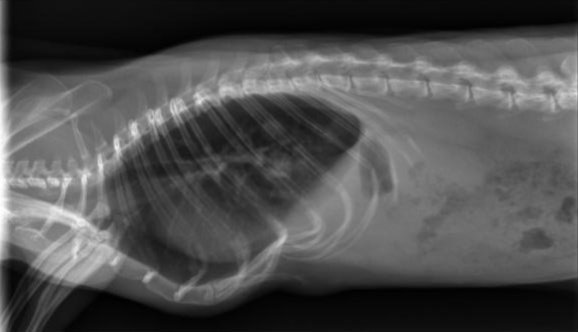

Certains d'entre vous ont vu passé en 2023 ici un sujet sur la naissance de ma 3ème portée: VIC Zelda & MAL Alpha. Et on ne vas pas se mentir, cette portée est fiasco... :( Nous avions eu 8 ratons nés le 07 mars 2023 et sur les 8, 3 déjà décédés dont 2 de soucis respiratoires. Nous avons sur cette famille commencé par Zéphyr, le frère de Zelda décédé en septembre 2023 après un long combat depuis avril. Une analyse avait été faite et révélait une bactérie ultra résistante et n'avait pas ressorti de mycoplasme. Quelques mois plus tard, Zelda a commencé à être touché par le même type de pathologie ainsi que son fils Björn. Après de longs traitements également, Zelda nous a quitté en juin et Björn en juillet alors que les traitements ne les soulageaient plus. Et a l'heure actuelle, je vois Cassian et Pénélope, toujours la même portée, développer à leur tour les mêmes symptômes. Ils sont actuellement sous traitement mais aucune analyse n'a été effectué. Je crains qu'une anesthésie lors du prélevement leur soit fatale. En revanche, des radios ont été effectués et ma vétérinaire à évoqué une fibrose pulmonaire, avec un stade plus avancé pour Cassian.

Je vous joint les radios de Cassian et Pénélope pour comparaison si vous avez également des radios de fibrose.

CASSIAN_corpsentier_face_1fibrose.jpg.9d0ebe9324977b38849b5a11505e62b9.jpgPENELOPE_corpsentier_face_1.jpg.c3f7df9c81ffd6672607b852461d1880.jpg